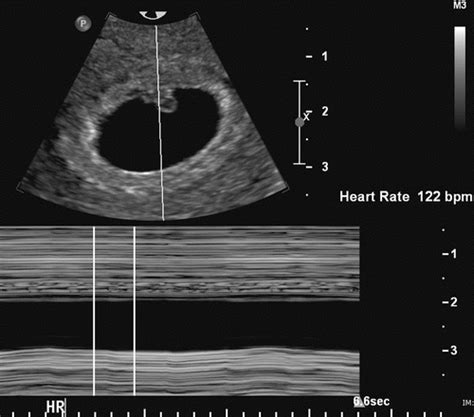

The normal fetal heart rate (FHR) is a crucial indicator of fetal well-being during pregnancy. A normal FHR typically ranges from 110 to 160 beats per minute (bpm), with an average rate of around 140 bpm. This range can vary slightly depending on the gestational age and the individual fetus. It's essential to monitor FHR regularly during pregnancy to detect any potential abnormalities or signs of fetal distress.

Fetal heart rate monitoring is typically performed using cardiotocography (CTG), which involves attaching sensors to the mother's abdomen to measure the fetal heart rate and uterine contractions. This non-invasive test provides valuable information about fetal well-being and can help identify potential complications early on. In addition to CTG, other methods such as Doppler ultrasound and fetal echocardiography can also be used to assess fetal heart rate and cardiac function.

- The normal fetal heart rate ranges from 110 to 160 beats per minute (bpm), with an average rate of around 140 bpm.